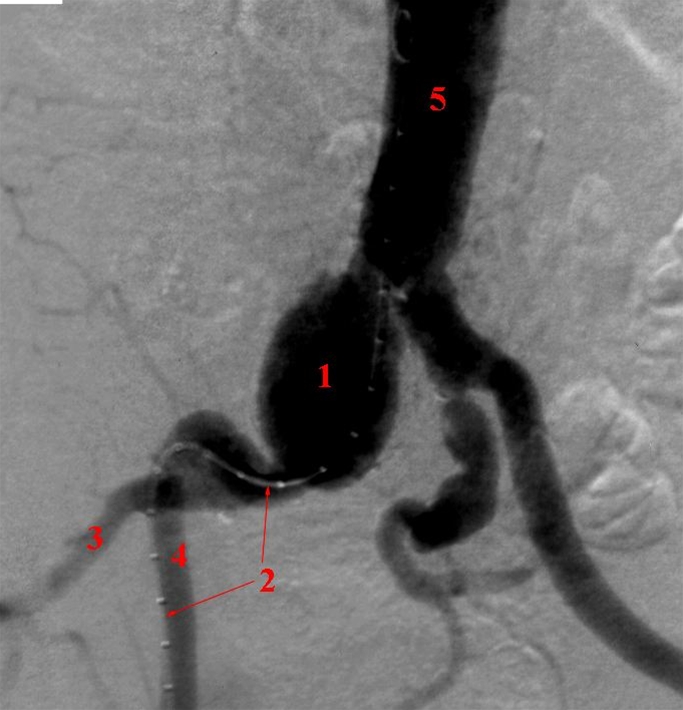

Røntgenkontrastundersøgelse (arteriografi) af legems- og bækkenpulsårerne (aorta og iliaca arterierne).

I højre bækkenpulsåre (arteria iliaca communis) ses en stor udposning (aneurisme) 1

1. Aneurisme (udposning)

2. Endovaskulært Kateter

3. højre a. iliaca interna/hypogastrica

4. højre a. iliaca externa

5. Aorta